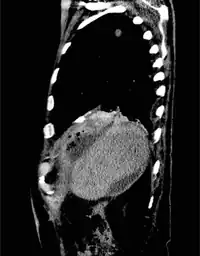

Biliary fistula

| Duodeno Biliary Fistula | |

For bronchobilary fistula, the following tests are performed: 1) ultrasound abdomen, may show subdiaphragmatic collection around the surface of the right lobe of the liver. 2) preoperative chest X-ray, may demonstrate mild to moderate right-sided pleural effusion without an active lung pathology. 3) CT scan, may reveal focal collection along the liver's right lateral margin, which can be communicating with one of the right lower lobe bronchi, supporting the diagnosis of a BBF.[1]